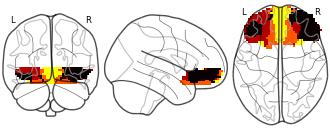

Connectivity-Based Parcellation of the Human Orbitofrontal Cortex: K=4...

EmailClick to copy linkLink copied Cite(2024). Connectivity-Based Parcellation of the Human Orbitofrontal Cortex: K=4 cluster map [Dataset]. http://identifiers.org/neurovault.image:887625niftiAvailable download formatsUnique identifierhttps://identifiers.org/neurovault.image:887625Dataset updatedNov 18, 2024License

Cite(2024). Connectivity-Based Parcellation of the Human Orbitofrontal Cortex: K=4 cluster map [Dataset]. http://identifiers.org/neurovault.image:887625niftiAvailable download formatsUnique identifierhttps://identifiers.org/neurovault.image:887625Dataset updatedNov 18, 2024LicenseCC0 1.0 Universal Public Domain Dedicationhttps://creativecommons.org/publicdomain/zero/1.0/

License information was derived automaticallyDescriptionK=4 cluster map based on N=13 participants.

Collection description

K-means cluster maps of orbitofrontal cortex with K=2, 3, 4, 5, 6, and 7 clusters based on resting-state fMRI data.